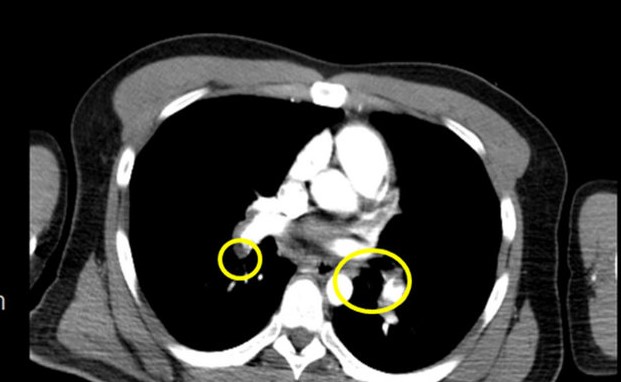

衛福部苗栗醫院急診室主任蔡昌宏今天指出,「肺栓塞」臨床症狀不明顯,一開始難以發現,卻有高致命性,死亡率高達30%以上,堪稱「隱形殺手」,主因是心臟通往肺動脈的血管突然被血塊、脂肪、空氣、組織碎片等形成的栓子阻塞,導致肺臟組織血液灌流不足,造成患者血中含氧量降低,出現低血氧症狀,包括呼吸困難、呼吸急促、肋膜性胸痛、腿部水腫、發汗、心悸、昏厥等。

蔡昌宏表示,這起案例是一名28歲年輕男性,在上班途中突感身體不適、盜汗,一路撐到公司門口即癱軟倒地,同事幫忙打119送抵醫院時,雖有意識,但臉色蒼白、全身無力、血壓低,說不出哪裡不舒服,經檢查發現有動脈血液缺氧現象,立即給予高濃度氧氣等緊急處置,並會診心臟內科,經電腦斷層檢查確診為肺栓塞,轉加護病房治療,一週後康復出院。